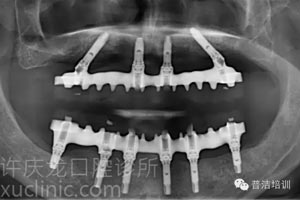

六、最終戴入患者口內的牙橋X光

![]() |

可以看到:種植體與上部牙橋各部件精密貼合,種植體植入的位置、角度等都堪稱完美。牙橋與牙齦的接縫經過特殊設計容易清潔,同時在說話或大笑的時候又不會露出來。